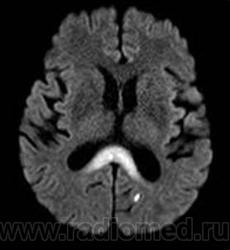

ГМ. Маркиафавы-Биньями болезнь. +

Маркиафавы-Биньями болезнь

Marchiafava, 1897, Bignami, 1903 – редко встречающийся вариант алкогольной энцефалопатии с патологистологичнски проявляющимся поражением (некрозом) мозолистого тела, образованием полостей в ткани мозга и развитием внутренней гидроцефалией. Клинически активная фаза заболевания длится от 2 до 6 лет, завершается она формированием глубокого слабоумия. В психотической стадии болезни наблюдаются слуховые и зрительные галлюцинации, апатия, депрессия, припадки, состояния возбуждения, спутанность сознания, картины псевдопаралича, а также разнообразные неврологические симптомы (тремор рук, дизартрия, абазия, арефлексия или гиперрефлексия, ослабление зрачковых реакций, изменение формы и величины зрачков и мн.др.). Лечение симптоматическое. Синонимы: Дегенерация мозолистого тела, Прогрессирующая алкогольная деменция